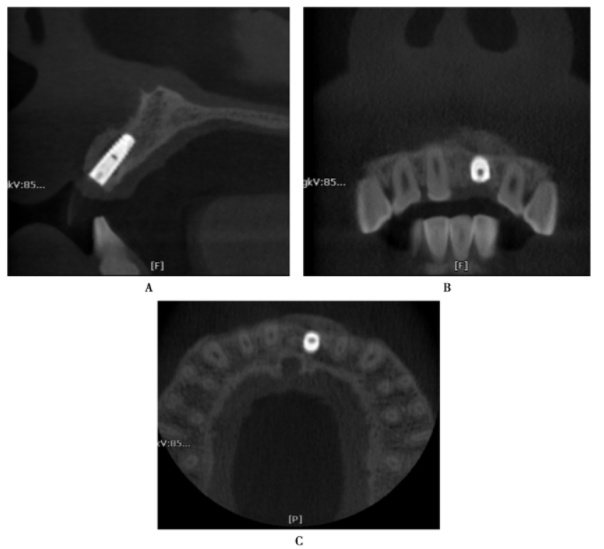

图19 同一患者前牙区即刻种植拔除残根唇侧植骨及种植术后矢状位、冠状位及水平位

可以清楚看见植入骨情况A.矢状位;B.冠状位;C.水平位

图20 前牙区牙折后即刻拔除牙后植入种植体

A.可见前牙牙折明显;B.即刻拔除牙后植入种植体,唇侧植入骨粉